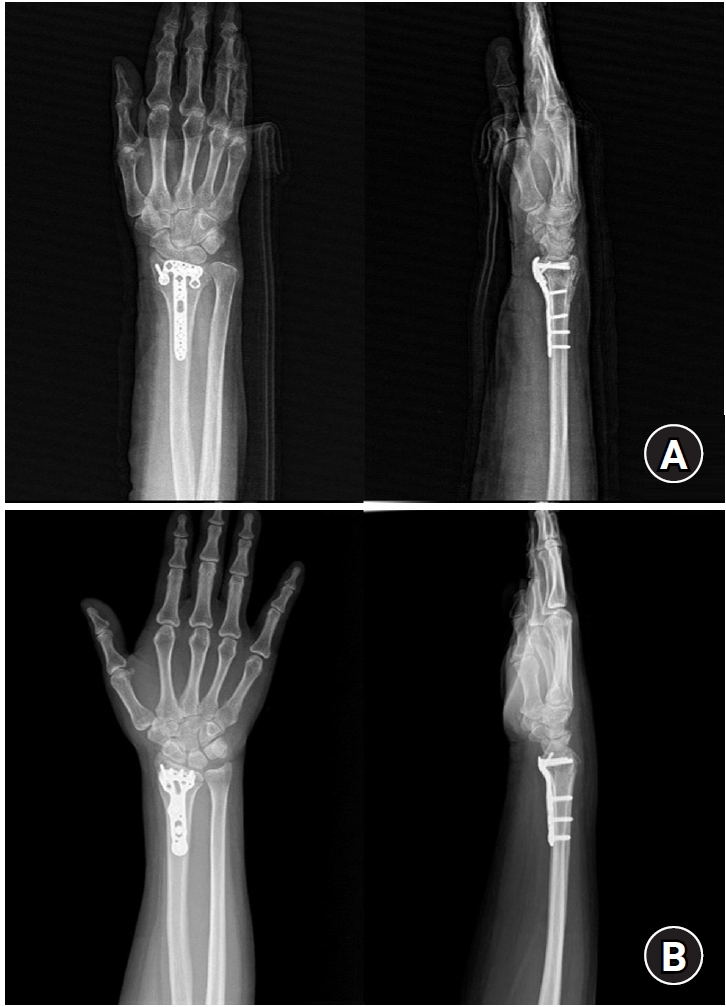

Standard anteroposterior and lateral radiographs were obtained at 2, 4, 6, and 12 weeks postoperatively to evaluate maintenance of reduction and radiographic union. At the final follow-up visit, wrist range of motion—including flexion, extension, pronation, and supination—was measured using a goniometer by an independent evaluator (Fig. 5).

Fig. 5.

Wrist range of motion—including (A) flexion, (B) extension, (C) pronation, and (D) supination—was measured at the final follow-up.

Fig. 5. Wrist range of motion—including (A) flexion, (B) extension, (C) pronation, and (D) supination—was measured at the final follow-up.